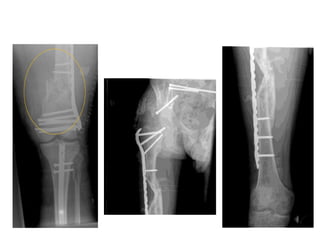

• Intertrochanteric/

Subtrochanteric fracture

treated with closed IM

Nail

• The goal:

• Restore length,

alignment, and

rotation

• NOT anatomic

reduction

• Without extensive

exposure this fracture

formed abundant callus

by 6 weeks

Valgus is restored...